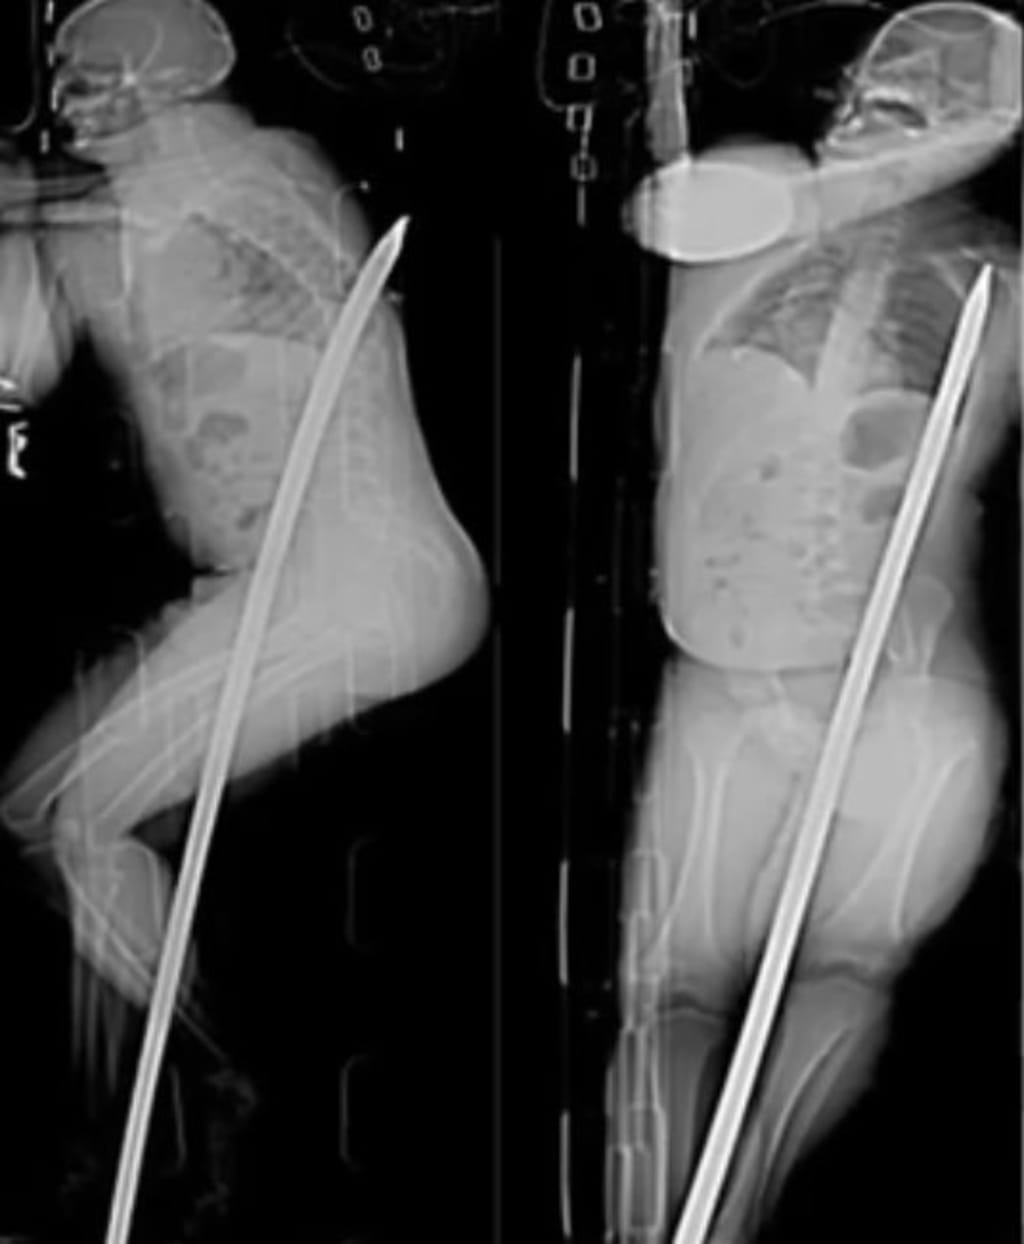

However, as he maneuvered the crowbar, the unexpected happened. De Wet slipped, and in an instant, his life was hanging by a thread. He fell onto the crowbar, which pierced his body in a gruesome and unimaginable manner. The five-foot metal rod entered through his groin area and exited just below his shoulder blade. The pain and shock were immediate and excruciating.

Upon arrival at the hospital, the gravity of De Wet's injuries became apparent. The metal rod had caused severe internal damage. It obliterated one of his kidneys and inflicted significant harm on his small intestine. The surgeons were faced with a daunting task: to extract the massive rod while minimizing further damage and preventing fatal complications.

The surgical team’s precision and expertise were critical. Over the course of several hours, they meticulously worked to remove the rod and repair the extensive internal injuries. The complexity of the surgery was heightened by the rod's path through De Wet's body, which had narrowly missed major arteries and vital organs. The fact that it had done so was nothing short of miraculous.